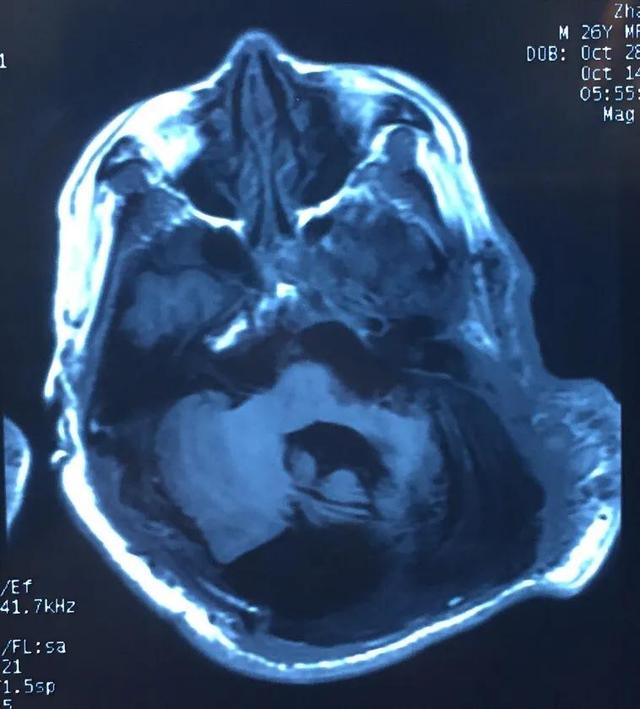

于是来到南昌市第三医院神经外科门诊,经过一系列的检查,头颅CT及MRI提示枕部存在一大一小颅骨缺损,其中大者达28*13cm,小脑萎缩明显,局部脑脊液充填,脑膜膨出伴少量脑膨出,要给如此巨大脑膜脑膨出行修补术,难度非常大,充分的术前检查、术前准备是必不可少的。

头颅MRV提示颅内静脉系统异常,窦汇、双侧横窦、乙状窦缺如,大量增生粗大引流静脉。头颅MRI未提示脑实质肿胀、梗塞、出血等表现。

术后第二天头颅CT复查未见脑积水形成,无异常出血。头颅CT三维重建提示颅骨缺损修补贴合良好。

术后第9天复查,仍无脑积水等异常表现。目前患者神志清楚,无发热,生命体征平稳,手术切口愈合良好,语言、肢体功能正常,无任何并发症发生,从此可以告别俯卧位睡觉,正常生活、学习、工作了。